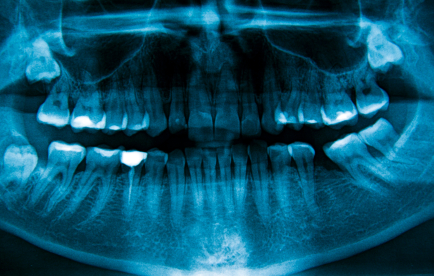

Ортопантомограма

Описание услуги - Ортопантомограма

Специальные рентгеновские, которая панорамное изображение зубов и челюсти. Тест проводится для определения полости зуба, или проблемы с костью челюсти, такие как переломы.

Типичные осложения:Увеличение воздействия рентгеновских лучей есть небольшой риск возникновения радиационно индуцированного рака в будущем.